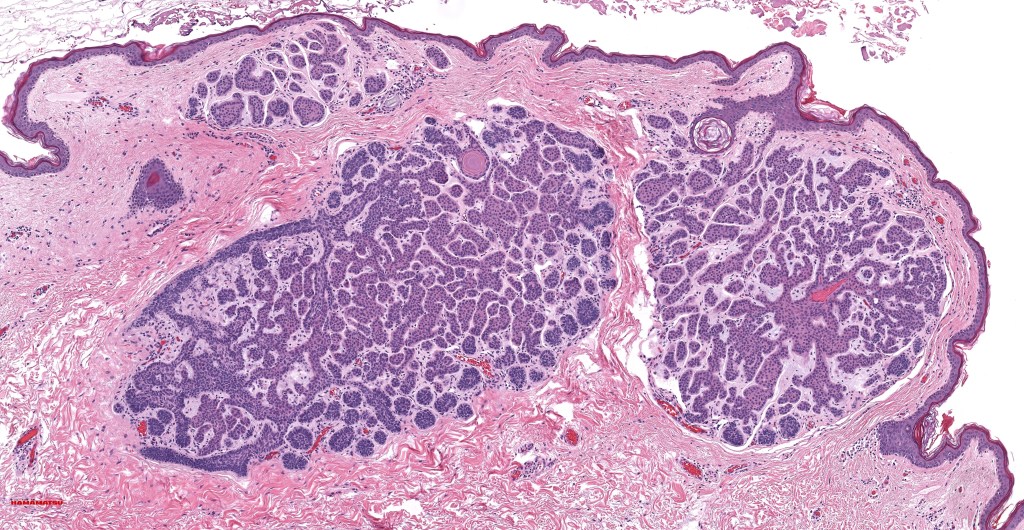

•Vertically orientated, folliculocentric, thin, anastomosing strands composed of basaloid cells embedded in a loose fibrous stroma

•Epidermal origin sometimes evident

•Variable keratocysts

•No retraction artifact or stromal mucin deposition

In the majority of cases, the diagnosis is straighforward. In case of any difficulty, basaloid follicular hamartoma can be distinguished from basal cell carcinoma by the absence of nodules, retraction artifact and stromal mucin deposition. The immunohistochemistry profile is quite different (see histology).